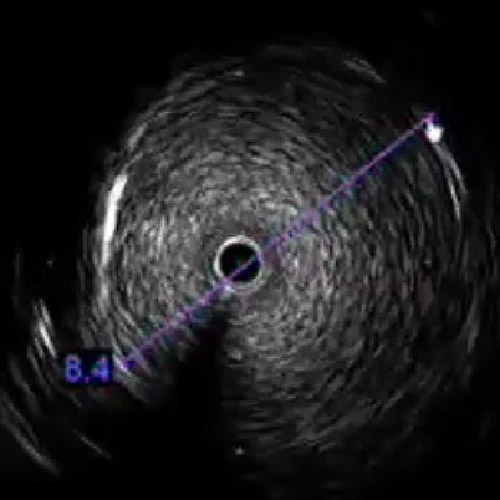

左dRAからエコーガイド穿刺を行いGlidesheateh Slender7FrとR2P SlenGuideの組み合わせでアプローチを開始した。その際、カバードステント(シャフト長135cm)の留置を予定していたため、よりガイディングカテのシステム全長を短くするためにR2P SlenGuideに止血弁を組み合わせた。R2P SlenGuideが病変部に対してコアキシャルになり難く、バックアップは十分に取れなかったが、6gワイヤー(0,014“)で病変を通過後、Navifocus WRでintra-plaque内であることを確認し、Senri 3-40mm でプレ拡張を行った(図3)(図4)。

レトログレードから6gワイヤー(0,014“)で病変を通過させ、AnteOwl WRで確認したところ、石灰化部で偽腔を通過していることを確認した(図3)(図4)。